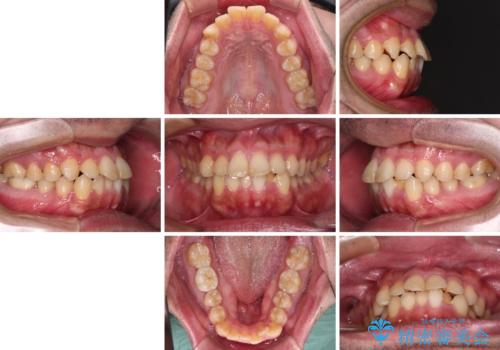

- 前歯のデコボコを治したいとのことで来院された患者様です。

できる限り楽して、短期間で治したいとのことで、ワイヤー装置にて矯正治療を行うこととしました。

インビザラインなどのマウスピース矯正は、楽に治療できると思われている方もいらっしゃると思いますが、毎日ストイックに22時間の装着を続けていくことは、決して楽なことではありません。

楽して治療したい方には、ワイヤー矯正がお勧めです。